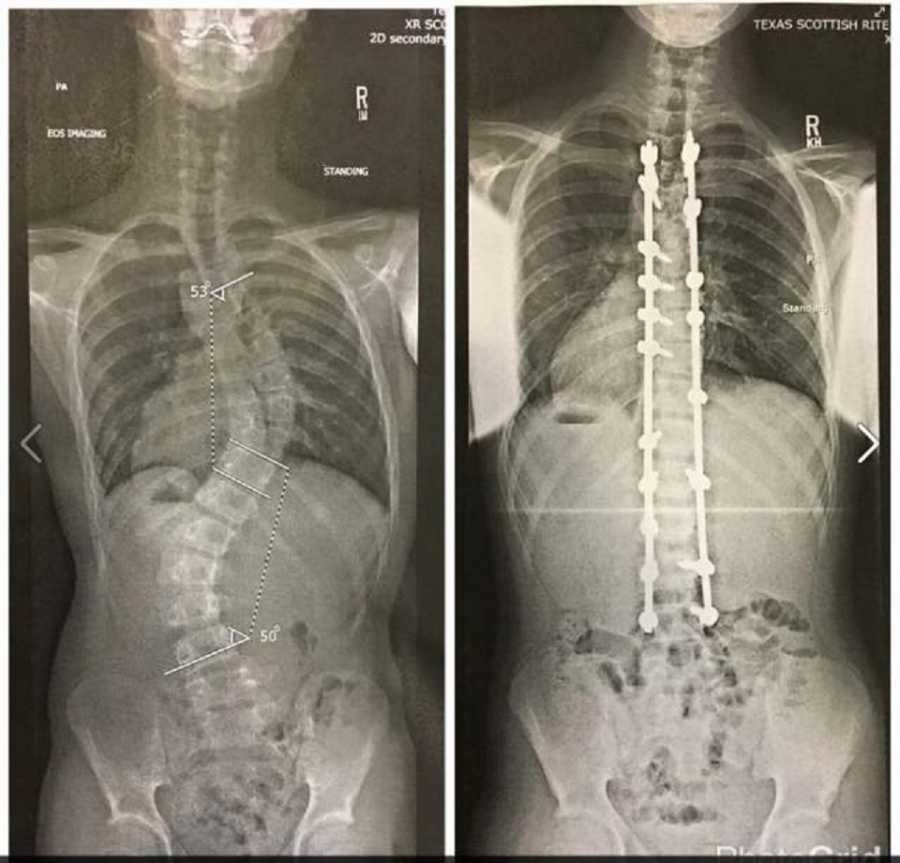

Aunque todo era perfecto, de pronto, Ciera tuvo que ser intervenida con una cirugía para corregir una severa escoliosis. El baile de graduación no sería una opción, no podría asistir, Ciera estaba profundamente triste, pero su inseparable amigo Connor supo cómo hacerla sentir bien.